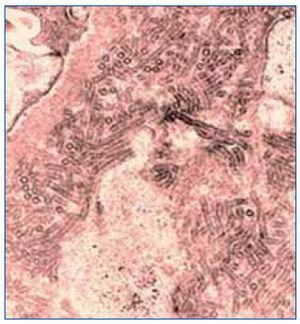

On light microscopy, glomeruli exhibited varying degrees of mesangial expansion, negative silver staining and congo red staining and some thickening of peripheral capillary walls. Immunoflourescence was positive only for IgG in mesangium and peripheral capillary walls. Electron microscopy showed microtubules >30 nm arranged focally in parallel in mesangium suggesting immunotactoid glomerulopathy (ITG) (figure 1). Further work-up showed a negative serum and 24-hr urine immuno-fixation electrophoresis. Imaging studies done for lymphoproliferative disease as an etiology were negative too.

Figure 1. Microtubular deposits of >30 nm seen in mesangium (on electron microscopy magnification x15000).